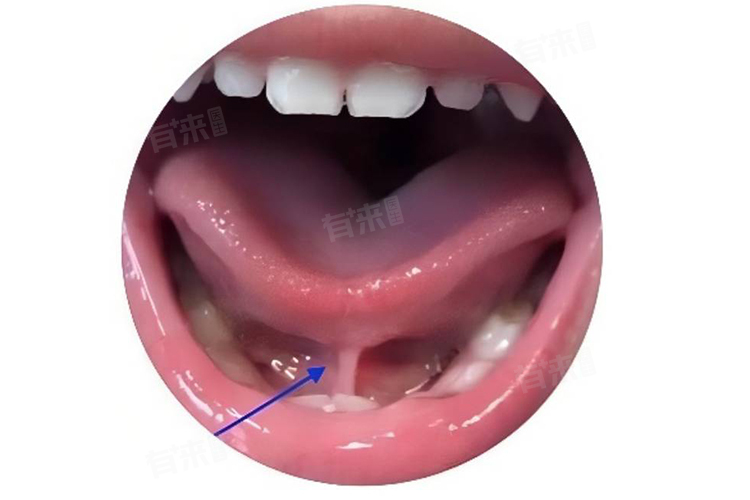

1、口腔科:如果儿童说话不清楚与口腔结构异常有关,如舌系带过短、唇腭裂等,口腔科将是重要的就诊科室。医生将检查儿童的口腔结构,评估是否存在影响发音的解剖因素,并可能提供相应的手术治疗或矫正方案。